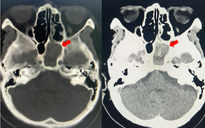

Trước đó, cụ bà N.T.G (91 tuổi, ngụ TP HCM) được người nhà đưa đến Khoa Cấp cứu-Bệnh viện Đa khoa Sài Gòn trong tình trạng khó thở nhiều, ho khạc đàm, đau tức ngực, sau khi điều trị tại cơ sở y tế khác nhưng không đáp ứng. Các bác sĩ xác định cụ bị suy hô hấp cấp trên nền bệnh tim, thận mạn và viêm phổi, một bệnh cảnh "nguy kịch chồng nguy kịch".

Ngay lập tức, ê-kíp cấp cứu đã tiến hành hỗ trợ thở không xâm lấn nhưng do tình trạng không cải thiện, các bác sĩ buộc phải đặt nội khí quản, thở máy và điều trị nội khoa tích cực. Các biện pháp hỗ trợ chức năng tim - thận, dùng kháng sinh, thuốc vận mạch đã được triển khai khẩn trương với mục tiêu kiểm soát tình trạng suy hô hấp và cải thiện toàn trạng.